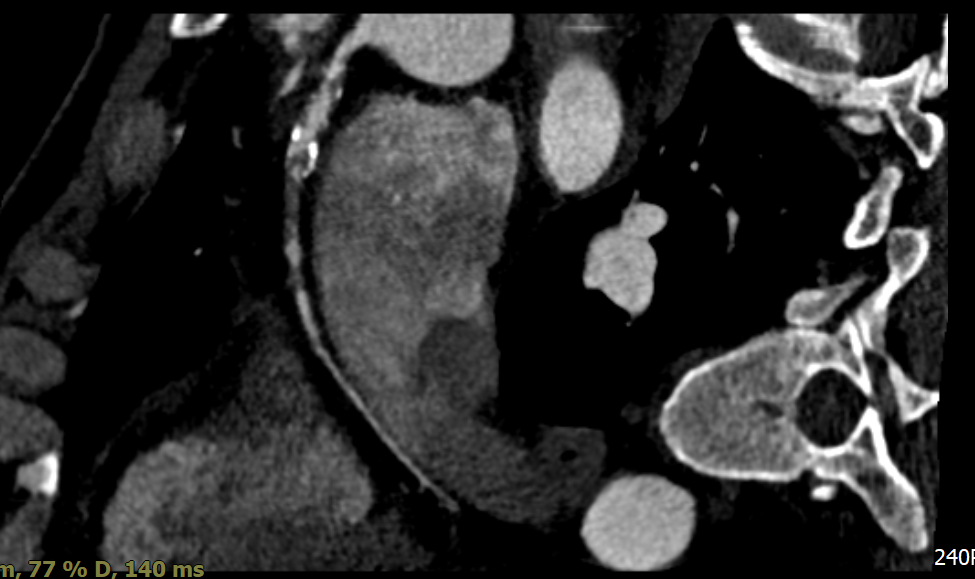

Coronary computed tomography angiography revealed a high calcium score of 1204.3 with focal occlusion and stenosis at the proximal LAD and proximal to mid RCA segments. Transthoracic echocardiography demonstrated preserved left ventricular systolic function (LVEF 61%) with mild hypokinesis of the basal anteroseptal wall.

Coronary angiography revealed three-vessel disease (SYNTAX score 29) with total occlusion of the proximal to mid LAD, 50% stenosis at the proximal LCX, and 70% stenosis at the distal LCX. The RCA showed chronic total occlusion from the proximal segment with collateral filling from both the LCX and LAD. The findings were consistent with acute anterior STEMI.

Because the patient presented with acute coronary syndrome, primary PCI was first performed for the culprit lesion, and a drug-eluting stent (DES) was implanted in the proximal LAD. A staged PCI with DES implantation to the proximal LCX was later performed. The initial antegrade attempt for RCA chronic total occlusion (CTO) failed despite wire escalations, as the guidewires could not cross the lesion. Considering the patient¡¯s intolerance and high contrast volume, the procedure was terminated. One month later, the patient was readmitted for complete revascularization. Antegrade wiring with a microcatheter and multiple guidewires (Fielder FC, ULTIMATEbros3, Conquest Pro) again failed to cross the RCA CTO. A retrograde approach using a SION wire via a septal collateral successfully reached the distal RCA. As the retrograde wire could not smoothly re-enter the true lumen, an antegrade wire was used to create a controlled subintimal hematoma, followed by the reverse CART technique. Anchoring balloon support then facilitated microcatheter advancement into the proximal RCA. The rendezvous technique achieved externalization with an ASAHI RG3 330 cm wire, and two Runthrough wires were advanced antegradely into the PDA and PL branches. After sequential balloon dilatation, two DESs (XIENCE Skypoint 2.75 ¡¿ 48 mm and 3.5 ¡¿ 38 mm) were deployed from the distal to the ostial RCA under IVUS guidance. Final angiography showed successful recanalization with TIMI 3 flow.